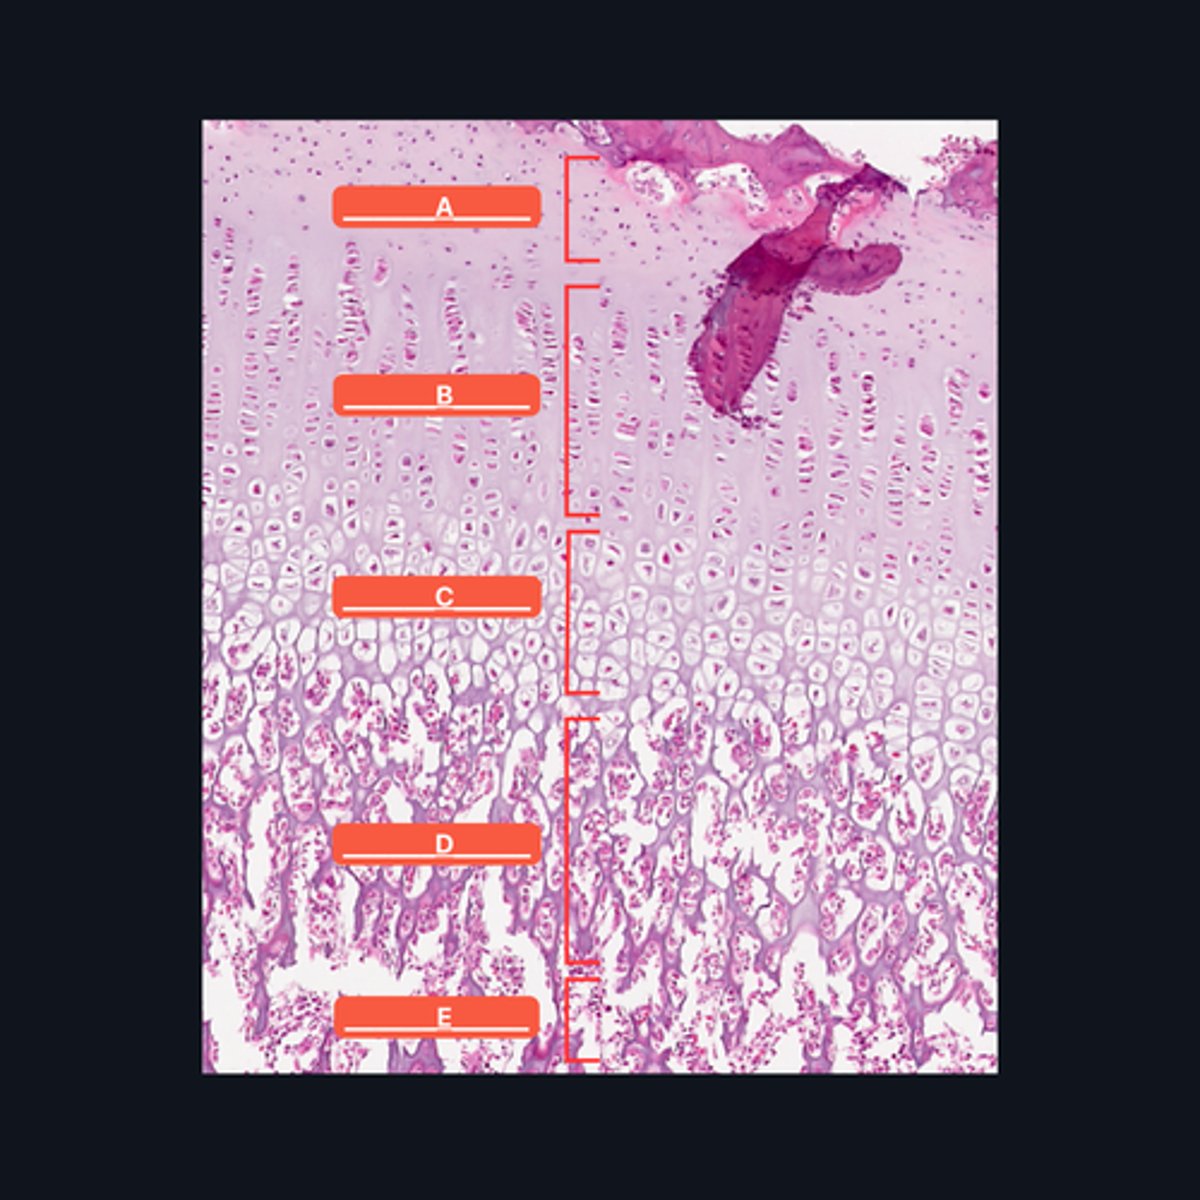

A - Zone of Resting Cartilage Cells

B - Zone of Proliferation

C - Zone of Maturation

D - Zone of Calcification

E - Zone of Ossification

Identify the pointed structures

B - Zone of Proliferation

Which pointed structure is the zone where instestitial growth occurs and what zone is it?

E - Zone of Ossification

Which pointed structure and what zone where many of the cavities left by cartilage cells merge to form marrow cavities?

C - Zone of Maturation

Which pointed structure and what zone do not divide anymore?

A - Zone of Resting Cartilage Cells

Which pointed structure and what zone anchors the epiphyseal plate to the epiphysis?

D - Zone of Calcification

Which pointed structure and what zone where the cartilage matrix is calcified